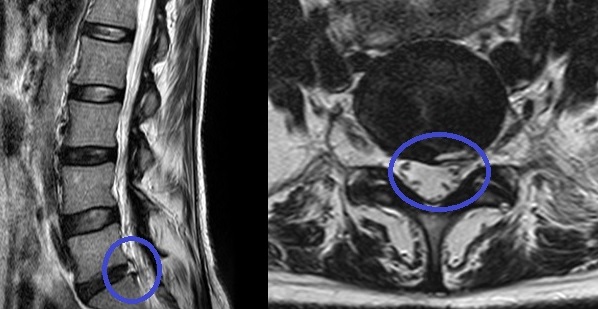

PELD (percutaneous endoscopic lumba discectomy) 내시경 레이저 디스크 수술은 허리 디스크로 인한 허리통증 및 하지 방사통을 완화하는 것을 목적으로 합니다. 허리 중앙에서 옆구리 10cm 정도 떨어진 위치에서 미세관을 디스크 속에 삽입하여 내시경을 이용해 모니터로 확인하면서 디스크에 병적인 수핵만을 제거하고 정상적인 수핵을 보존하는 수술입니다. 보존 요법과 수술 요법 사이에 있는 미세 또는 최소 침습 치료법으로 레이저를 사용하여 신경 압박으로 통증을 유발하는 수핵만을 제거하는 비관혈적 시술로 절개수술이 아니므로 신경, 근육에 손상을 주지 않습니다.